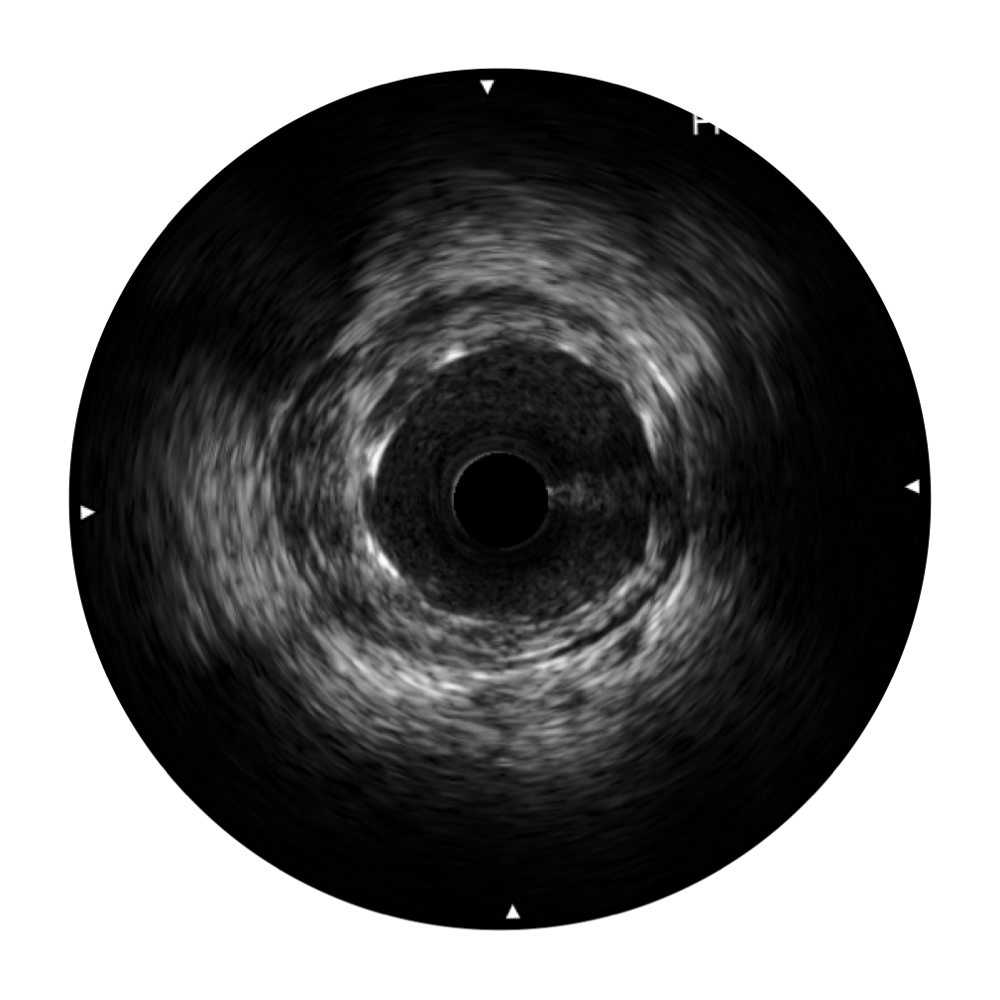

玖鼎集团宽频IVUS图像

传统IVUS图像

对比传统IVUS导管成像,玖鼎集团宽频IVUS图像的近场支架梁显影更细腻,远场中膜外血管仍清晰可辨,兼顾远中近,兼顾分辨力与穿透深度